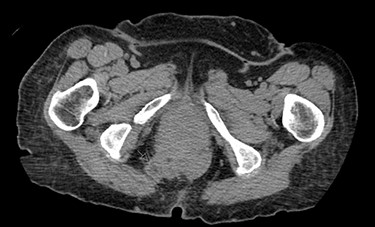

A 62-year-old post-menopausal female presented with worsening fecal urgency, incontinence and a corresponding perianal bulge that was increasing in size over the past 2 years. The patient had a recent history of significant weight loss through diet modification. Medical history was significant for two previous vaginal deliveries, 15-pack per year smoking history, hypothyroidism, hiatal hernia, previous CVA and chronic obstructive pulmonary disease. Fifteen years prior, the patient underwent a total vaginal hysterectomy, including a McCall culdoplasty, anterior and posterior repairs, sacrospinous ligament suspension and tension-free vaginal taping to treat symptomatic cystocele, rectocele and descent of the uterus. A previous computed tomography (CT) demonstrated a heterogeneously enhancing mass extending from the right posterolateral margin of the lower vaginal cuff and perirectal region into the ischioanal fossa, suggestive of, but not definite for a soft tissue mass (Fig. 1). Upon clinical exam, the patient was noted to have a defect in the right levator muscles complex with complete herniation of her rectum through this defect. This hernia created pocking of the stool and difficulties with stool emptying. In addition, the patient had to adjust her sitting position to avoid unwanted stool leakage as a result of spontaneous hernia reduction. The patient was offered an abdominoperineal resection; however, discussion of laparoscopic interventions with the DaVinci robot quickly became the best option for repair. Informed consent was obtained for robotic repair, and routine preoperative colonoscopy was performed.

Post-operative CT demonstrating mild fluid in pelvis and resolution of the hernia (black arrow).